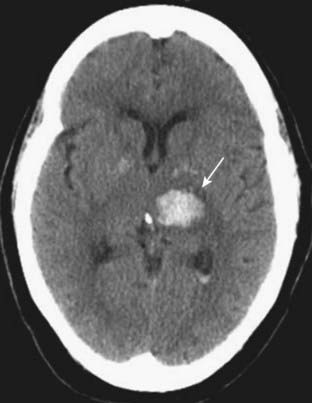

image

Figure 25-18 Intracerebral hemorrhage, acute.

Freshly extravasated whole blood, as this bleed into the thalamus (solid white arrow), will be visible as increased density on nonenhanced CT scans of the brain due primarily to the protein in the blood (mostly hemoglobin). As the clot begins to form, the blood becomes denser for about 3 days because of dehydration of the clot. After the third day, the clot gradually decreases in density from the outside in and becomes invisible over the next several weeks.